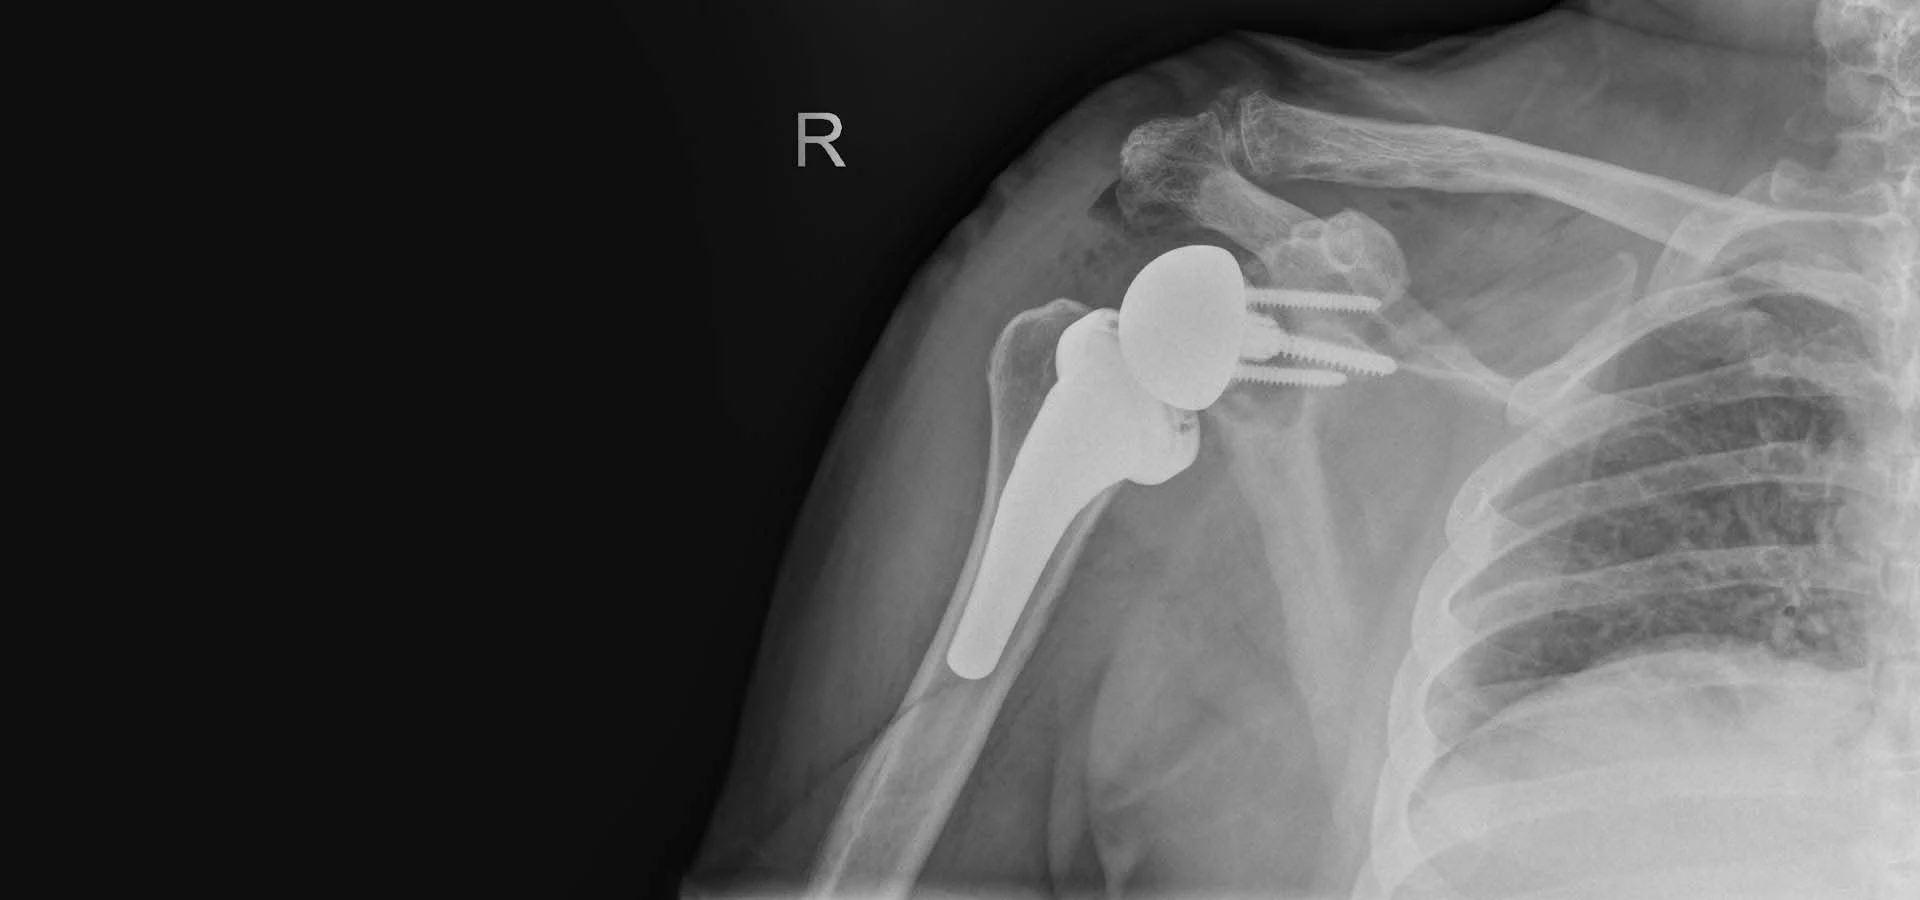

Μελέτη περίπτωσης: Εξατομικευμένη Ανάστροφη Ολική Αρθροπλαστική Δεξιού Ώμου σε Ασθενή με Βαριά Παραμορφωτική Αρθρίτιδα

Η 59χρονη ασθενής αντιμετώπιζε πολύ έντονο πόνο στον ώμο και το χέρι και παρουσίαζε σοβαρή δυσκαμψία στο εν λόγω σημείο. Όπως χαρακτηριστικά δήλωνε και η ίδια «δεν μπορούσε να χρησιμοποιήσει καθόλου το χέρι της και πονούσε όλη μέρα και κάθε βράδυ».

Μία από τις πρώτες ενέργειες που έλαβαν χώρα, ήταν η λήψη ενός ενδελεχούς ιατρικού ιστορικού. Στη συνέχεια, σειρά είχε η λεπτομερής κλινική εξέταση της ασθενούς, όπως και οι απεικονιστικές εξετάσεις (ειδικές ακτινογραφίες, αξονική και μαγνητική τομογραφία). Εν τέλει, διαπιστώθηκε πως η ασθενής έπασχε από βαριά παραμορφωτική αρθρίτιδα με οστικές παραμορφώσεις.

Η ασθενής υποβλήθηκε λοιπόν σε ανάστροφη ολική αρθροπλαστική του ώμου, η οποία αφορά την εμφύτευση τεχνητών επιφανειών στην άρθρωση του ώμου οι οποίες τοποθετούνται αντιστρόφως.

Πιο συγκεκριμένα, το μεταλλικό ημικύκλιο της σφαίρας που αντικαθιστά την κεφαλή του βραχιονίου οστού, τοποθετείται στην ωμογλήνη, την υποδοχή της ωμοπλάτης. Το πρόθεμα αυτό σταθεροποιείται αρχικά με μία πανίσχυρη κεντρική βίδα καθώς και ειδικές περιφερικές βίδες. Στη συνέχεια τοποθετείται ένας στειλεός στο βραχιόνιο. Αυτά κουμπώνουν μεταξύ τους με ένα πλαστικό πολυαιθυλένιο. Με αυτό τον τρόπο λοιπόν έχουμε  ένα εξαιρετικά δυνατό και σταθερό νέο ώμο, ο οποίος επιτρέπει την κίνηση προς κάθε κατεύθυνση και δύναται να πάρει οποιοδήποτε φορτίο. Εμβιομηχανικά, μετατοπίζεται το κέντρο περιστροφής της άρθρωσης προς τα κάτω και προς τα έξω, βελτιώνοντας έτσι την τάση του δελτοειδούς μυός, αλλά και των παρακείμενων ιστών, μαλακών μορίων και μικρών τενόντων του ώμου, του λεγόμενου στροφικού πετάλου.